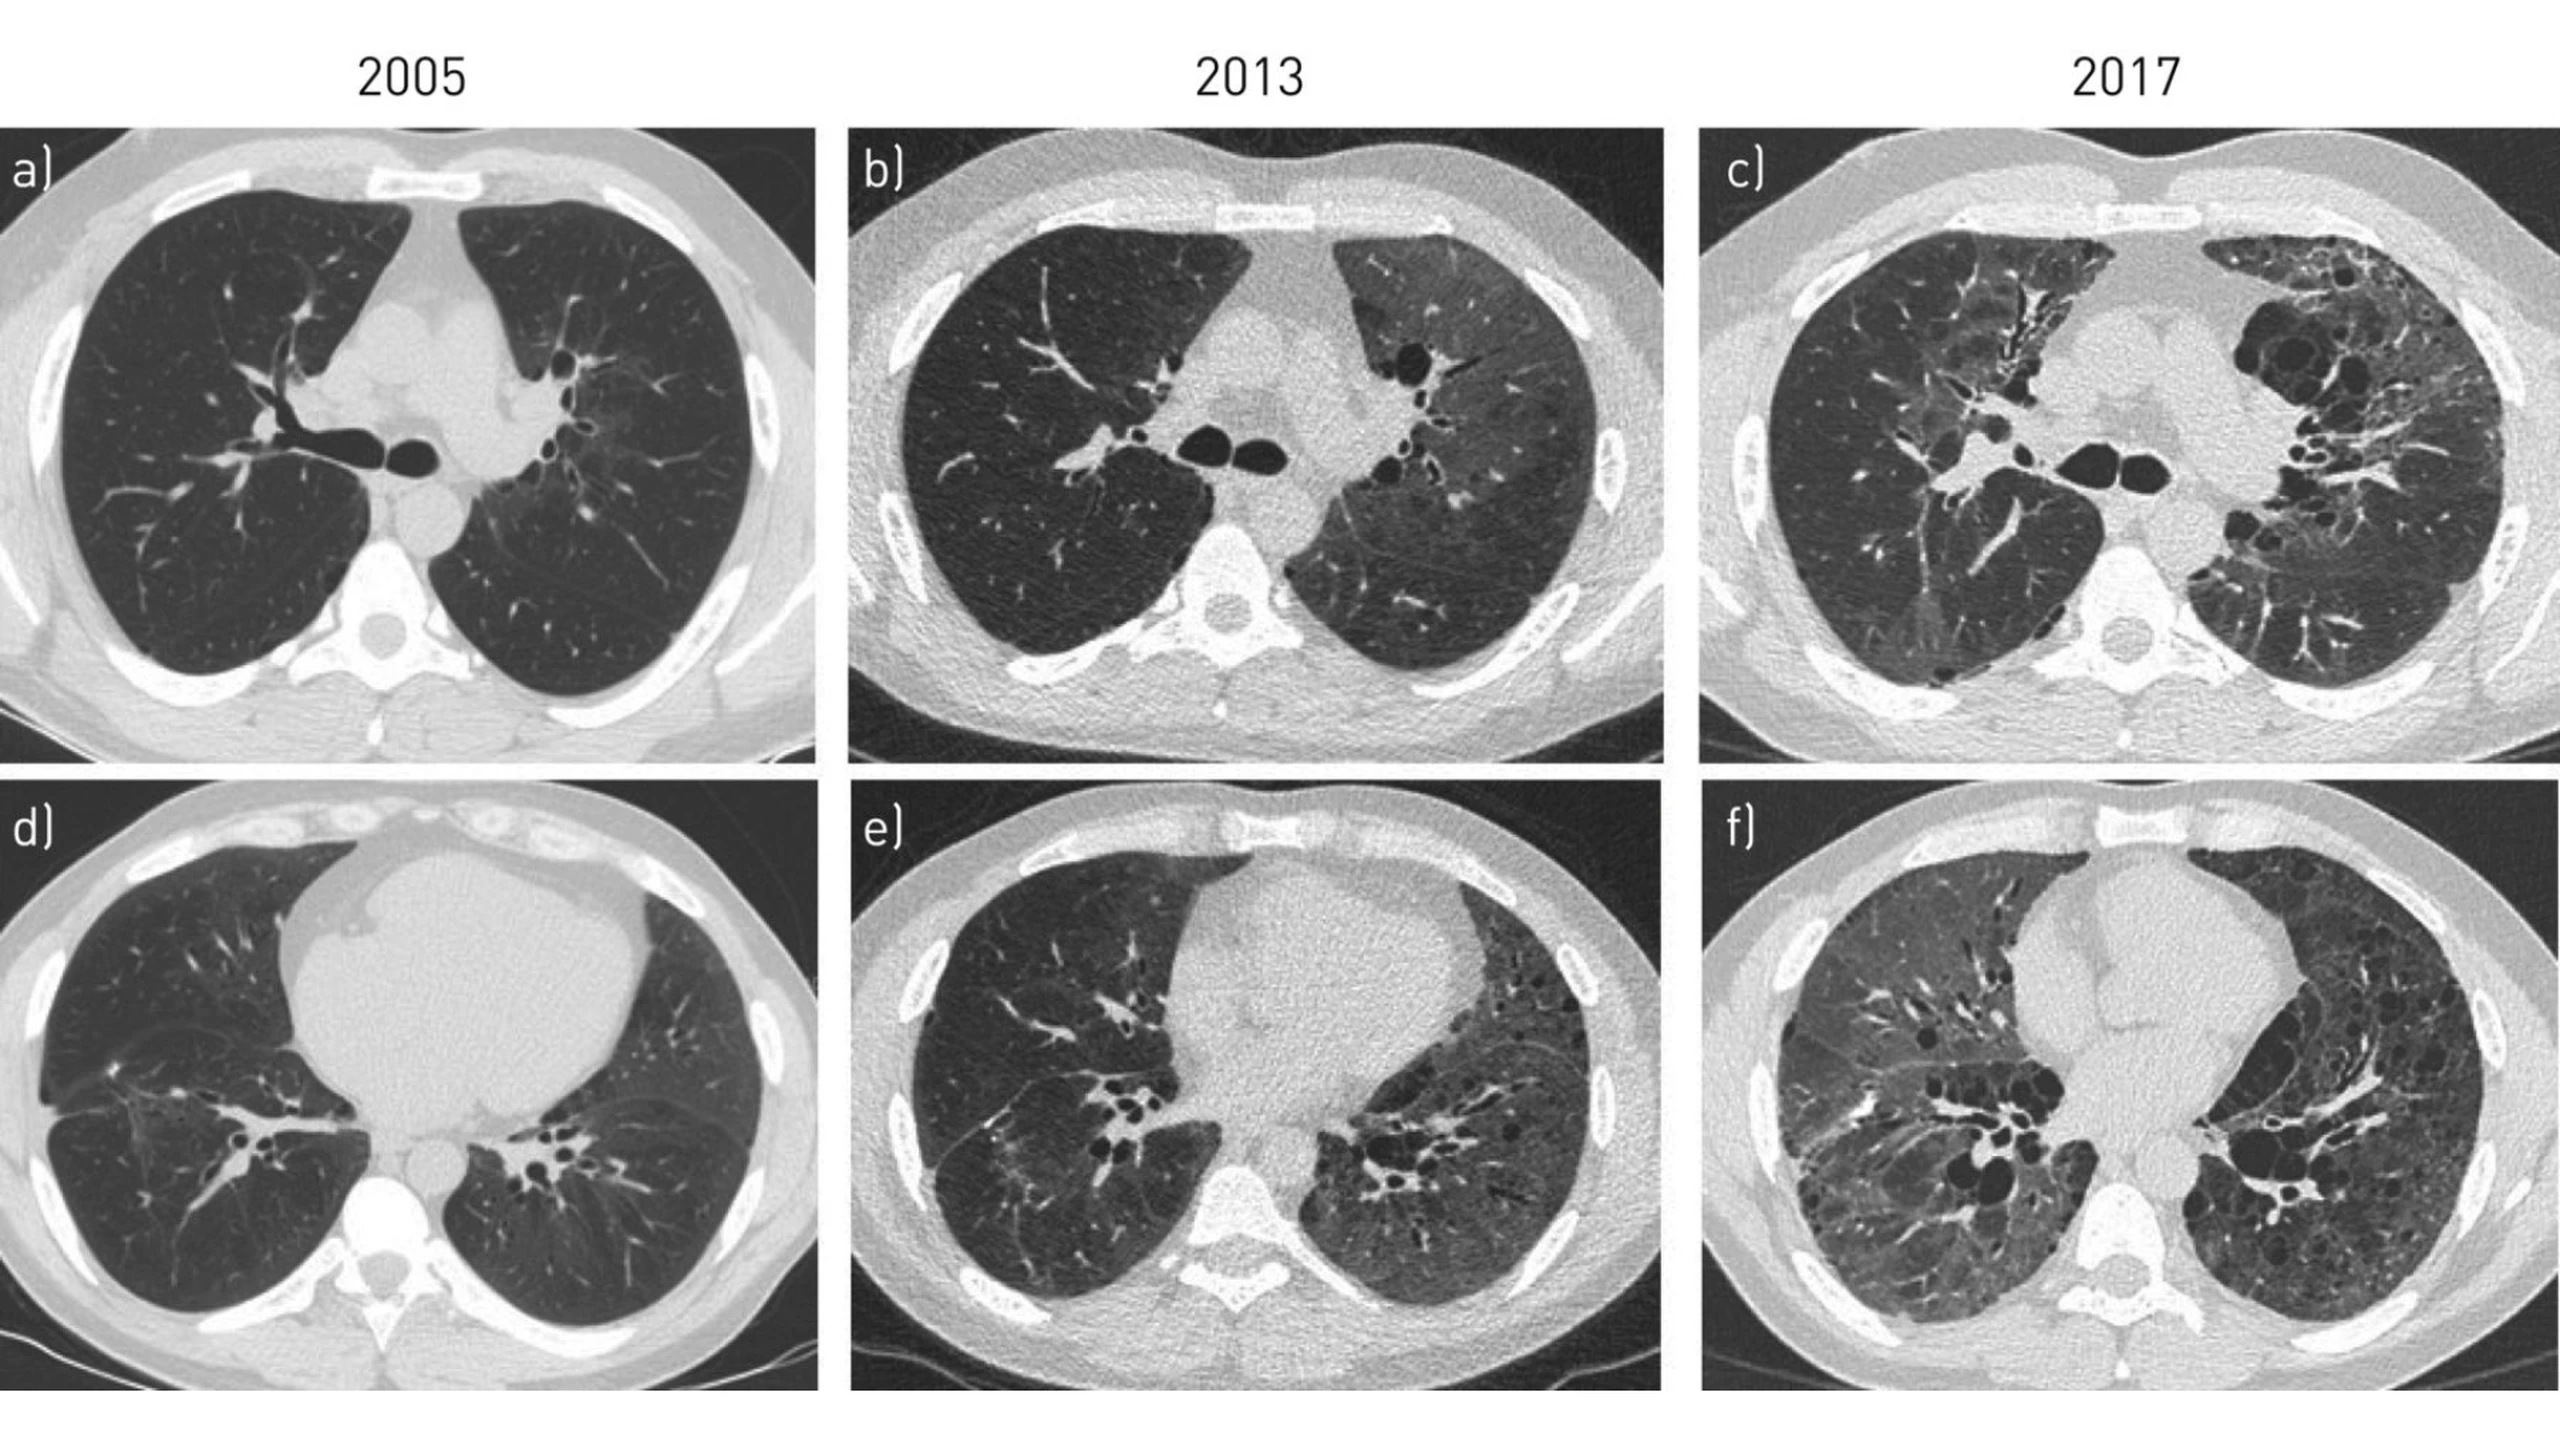

Viêm phổi kẽ tróc vảy (Desquamative interstitial pneumonia - DIP) là một bệnh gây ra bởi đại thực bào xâm nhập vào phế nang, viêm kẽ và xơ hóa phổi. Khoảng 90% các trường hợp viêm phổi kẽ tróc vảy có liên quan đến hút thuốc lá, người làm việc trong môi trường khói bụi thường xuyên.

Viêm phổi kẽ tróc vảy là một dạng viêm phổi kẽ vô căn có số lượng đại thực bào tăng cao trong phế nang (túi khí) của phổi. Các đại thực bào phế nang có sắc tố màu nâu nhạt đặc trưng và tích tụ trong lòng phế nang và vùng vách ngăn của thùy dưới của phổi. Các tác động điển hình của sự tích tụ đại thực bào là viêm và sau đó là xơ hóa (dày lên và cứng) của mô phổi. Viêm phổi kẽ tróc vảy là một loại viêm phổi kẽ nguyên phát chủ yếu liên quan đến hút thuốc, phơi nhiễm chủ động hoặc thụ động với khói thuốc lá.

Viêm phổi kẽ tróc vảy là một bệnh phổi kẽ phổ biến nhất liên quan đến hút thuốc lá. Nó gây ra các triệu chứng hô hấp bao gồm ho khan và khó thở tăng dần. Các phát hiện đặc trưng trên chụp CT bao gồm mờ kính mờ hai bên, vách ngăn dày lên và cấu trúc phổi vẫn được bảo tồn.